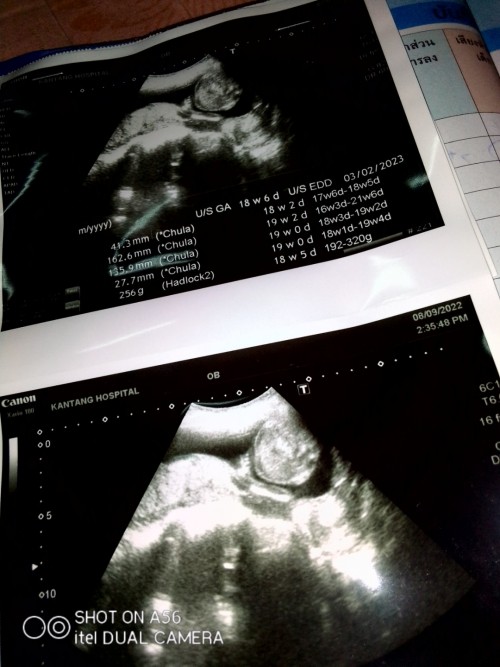

โชว์ไป1กรุบจ้า55 สมใจพ่อเขาเลย ลูกชาย🥰 #19W4